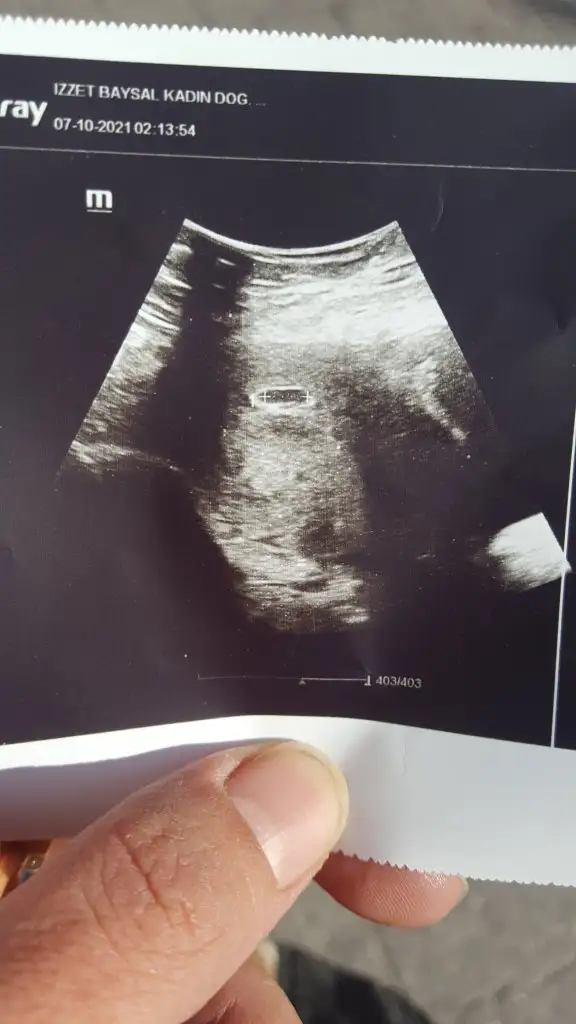

6+1 şuan kızlar. Kese büyüyor ici boş görünüyordu hem alttan hem üstten bakıldı. Haftaya çarşamba gel dedi belki biz göremiyoruz dedi sakin ol hala hamilesin bekle dedi

Merhabalar kızlar. Bende nokta leke oldu. Doktora gittim hem alttan hem üstten bakıldı kese göründü ama bebekyok boş olabilir dedi. Çok sarsıldım rabbim hayırlısını nasip etsin

6+1 bugün kuzum alttanda baktı malesef göremedik kese büyümüş ama içi boştu. Inşallah haftaya çarşamba bekliyoruz

Ultrason fotoğrafın var mı? Alttan baktı bana direkt üsten denemedi bile görünmez çok küçük dedi

Ultrason fotoğrafını vermedi bana ama gösterdi keseyi. Bende şaşırdım ama birşey demedim keseyi gördüm rahatladığım için. Hatta sordum hocam normal mi diye erken daha normal kafana takma tekrar 1 hafta 10 gün sonra bakalım dedi. Bebeği görelim dedi.